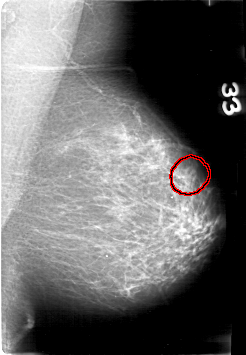

D_4089_1.RIGHT_MLO

LEFT_MLO LINES 5311 PIXELS_PER_LINE 3676 BITS_PER_PIXEL 12 RESOLUTION 43.5 OVERLAY

FILE: D_4089_1.LEFT_MLO.OVERLAY

TOTAL_ABNORMALITIES 1

ABNORMALITY 1

LESION_TYPE MASS SHAPE OVAL MARGINS OBSCURED

ASSESSMENT 0

SUBTLETY 3

PATHOLOGY BENIGN

TOTAL_OUTLINES 1

BOUNDARY